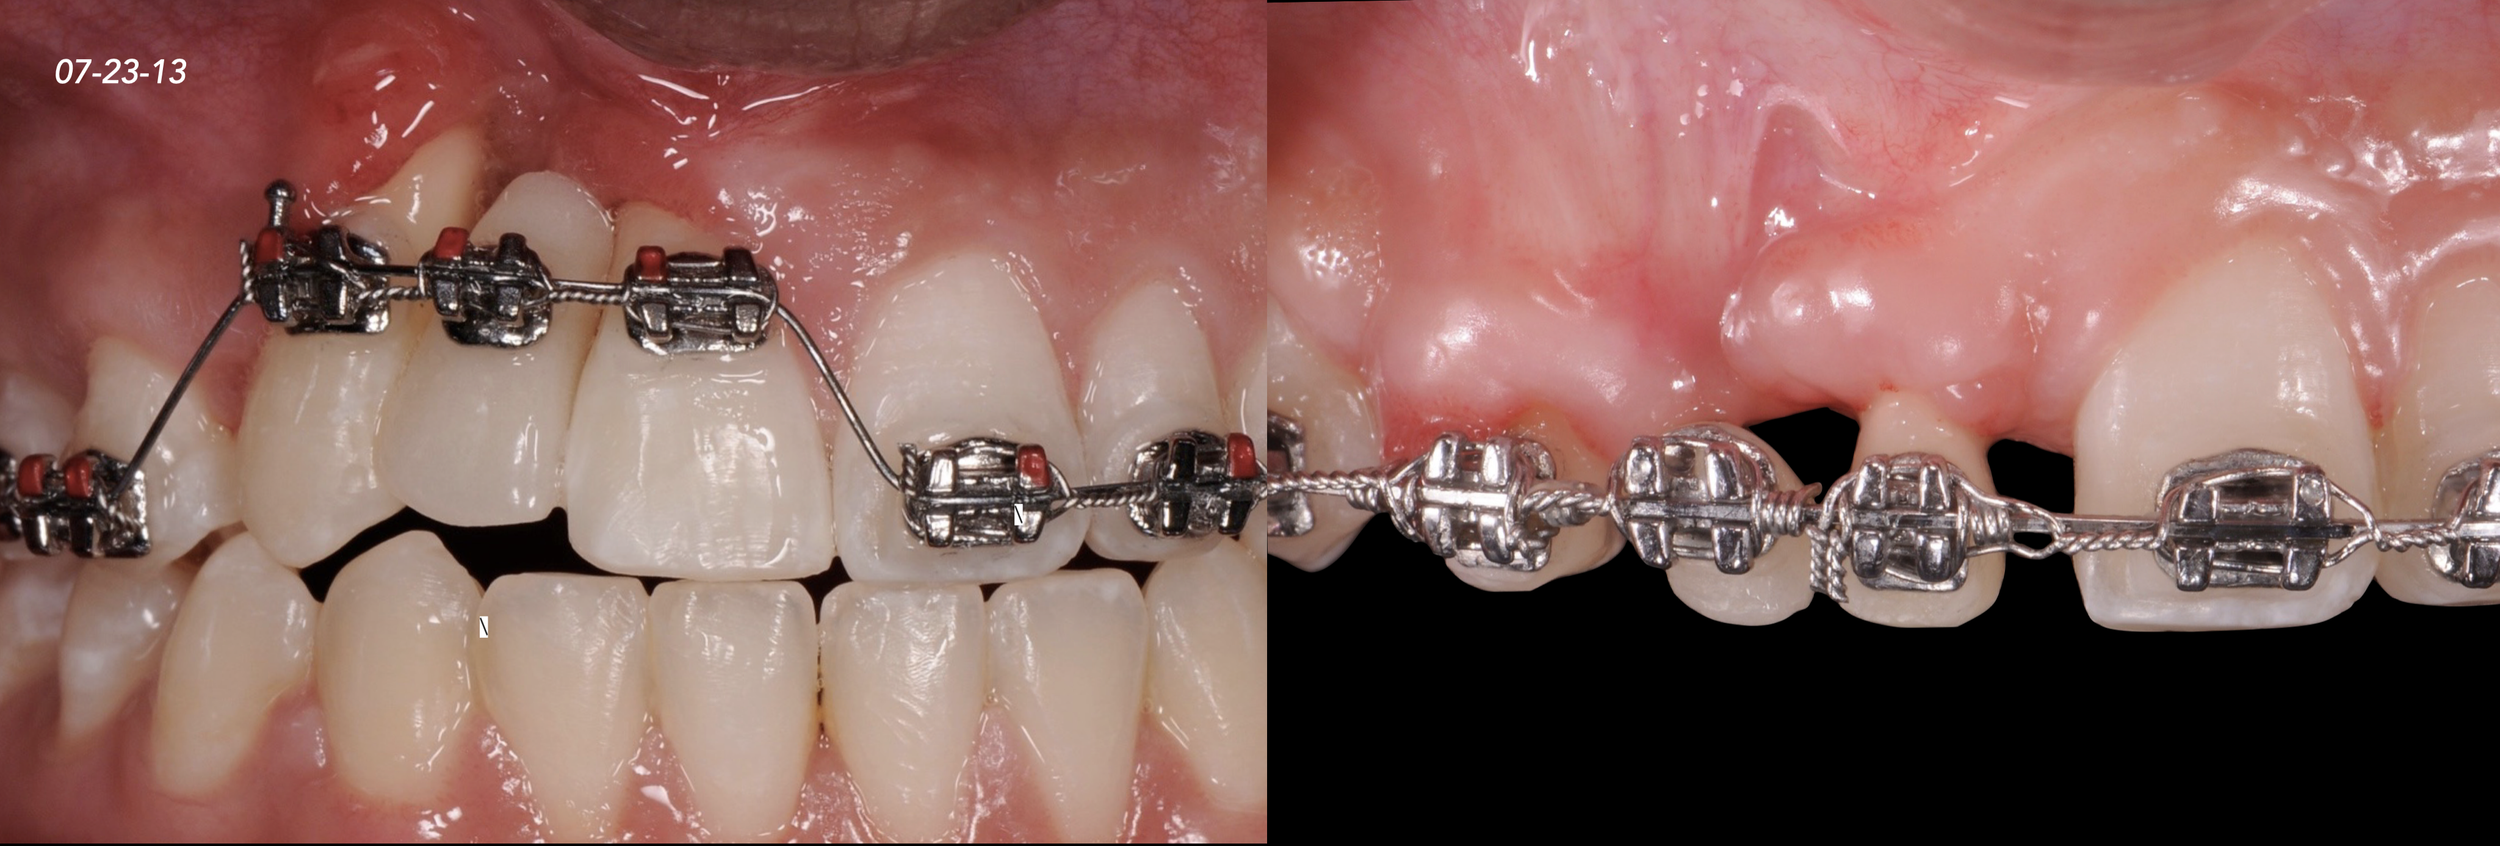

CASE 1. COMPLEX IATROGENIC DEFECT